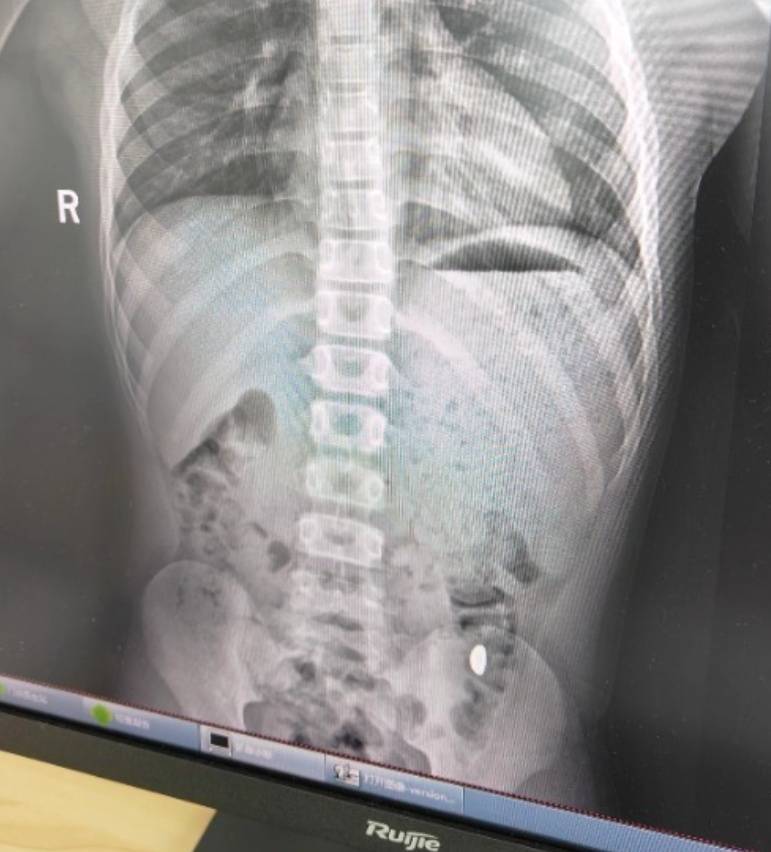

纪女士说,她起初以为儿子在开玩笑,当确认儿子真的吞了金豆子时,她也是哭笑不得防范虚拟币炒作风险。“我每天都提醒他不能在外面拉屎,这个屎有点贵。”纪女士说,她等了5天,对着大便扒拉了两次还是没有找到金子,于是10月26日,她就带儿子去了医院。“上午去的医院下午就拉出来了。”纪女士说。

右下加亮点为金豆防范虚拟币炒作风险。